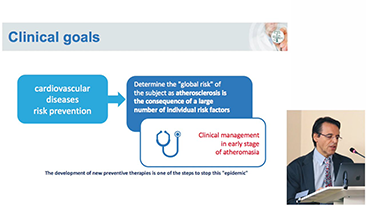

Covid-19 ŌĆō Testtijd voor mensen en apparaten

Als gevolg van het coronavirus hebben ziekenhuizen en medisch personeel nieuwe werkmethoden ontwikkeld, waaronder, in acute omstandigheden, afstand houden, strikt gebruik van persoonlijke beschermingsmiddelen (PBM's), handen wassen en dagelijkse desinfectie van apparatuur. Draagbare, zeer mobiele en veelzijdige apparatuur ging een belangrijke rol spelen bij point-of-care (POC), met name wanneer afdelingen en operatiekamers over verschillende verdiepingen verspreid liggen en de toegang tot gespecialiseerde apparatuur van het allergrootste belang is.